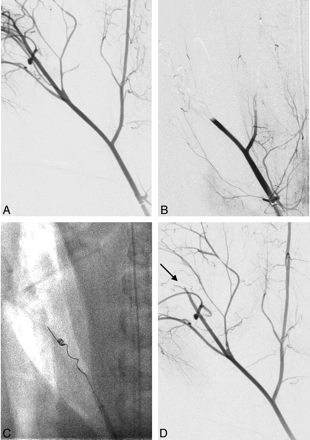

A total of 16 vessels (6 LAs, 8 SCAs, and 2 IMAXs) were occluded, and 48 retrieval attempts were made. A total of 8 vessels were successfully occluded with erythrocyte-rich clot (group A), and 8 vessels were occluded with fibrin-rich clot (group B). The Table summarizes the data and statistical significance between the 2 groups. In every target vessel, microcatheterization through the occlusion site was successfully achieved. Fourteen retrieval attempts were made to achieve the final angiographic results in the target arteries in group A, whereas 34 attempts were made in group B (P < .001). Every target vessel (100%) in group A achieved recanalization of TIMI grade 2 or greater, whereas only 3 of 8 vessels (37.5%) achieved recanalization of TIMI grade 2 or greater in group B. Figures 2 and 3 show the typical angiographic findings from each group. The average number of retrieval attempts to achieve the angiographic end point was 2.75 times in group A and 4.5 times in group B (P < .001). In group A, 3 vessels demonstrated TIMI grade 3 recanalization with 1 retrieval attempt, 2 vessels showed TIMI grade 3 recanalization after 2 attempts, 2 vessels achieved TIMI grade 2 recanalization after 2 attempts, and 1 vessel showed TIMI grade 2 recanalization after 3 attempts. In group B, 1 vessel achieved TIMI 3 recanalization after 2 attempts, 1 vessel achieved TIMI 2 recanalization after 3 attempts, and 1 vessel achieved TIMI grade 2 recanalization after 4 attempts. The remaining 5 target vessels in group B did not demonstrate significant vessel recanalization (1 vessel with TIMI 1 after 5 attempts and 4 vessels with TIMI 0 after 5 attempts) (Fig 2).

Angiographic findings of a target vessel occluded with an erythrocyte-rich clot and treated with MT. A, Preprocedural angiogram of a right superficial cervical artery (anteroposterior view) shows the branching pattern of the artery. B, Complete occlusion of the vessel was confirmed after injection of an erythrocyte-rich clot. C, A Merci clot retriever device (V2.5 firm) was deployed distal to the occlusion site, and clot retrieval was performed. D, A postprocedural angiogram shows recanalization of the treated artery. Small residual thrombi distal to the bifurcation of the artery are also seen (arrow).

The average time required to achieve the final angiographic result was 15.5 minutes in group A and 81.5 minutes in group B (P < .01). Figures 3 and 4 show the typical angiographic findings from each group. All of the 8 target vessels in group A demonstrated recanalization (TIMI 2 or greater), and 7 of 8 demonstrated distal migration of the fragmented clot. In group B, only 3 of the 8 target vessels demonstrated recanalization, and 2 of 3 demonstrated distal migration of the fragmented clot. No vessel dissection or perforation was observed in the postprocedural angiograms.